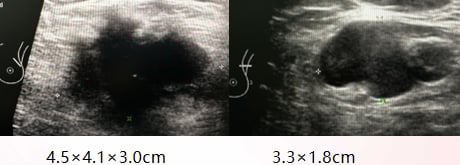

患者为33岁年轻女性,身体状况良好(ECOG 0分)。2023年10月,因发现乳房肿物就诊,超声检查提示左乳存在一个约4.5cm的巨大实性肿块,且腋下淋巴结已出现肿大。穿刺活检病理证实为乳腺浸润性癌,免疫组化结果显示:ER(80%强+), PR(60%强+), HER2(2+),Ki67(40%),属于Luminal B型HER2阳性乳腺癌。然而,患者当时未选择规范治疗,转而寻求中医药治疗,这为后续病情的快速恶化埋下了隐患。

- 乳房及淋巴结:原发灶及肿大淋巴结均显著缩小。